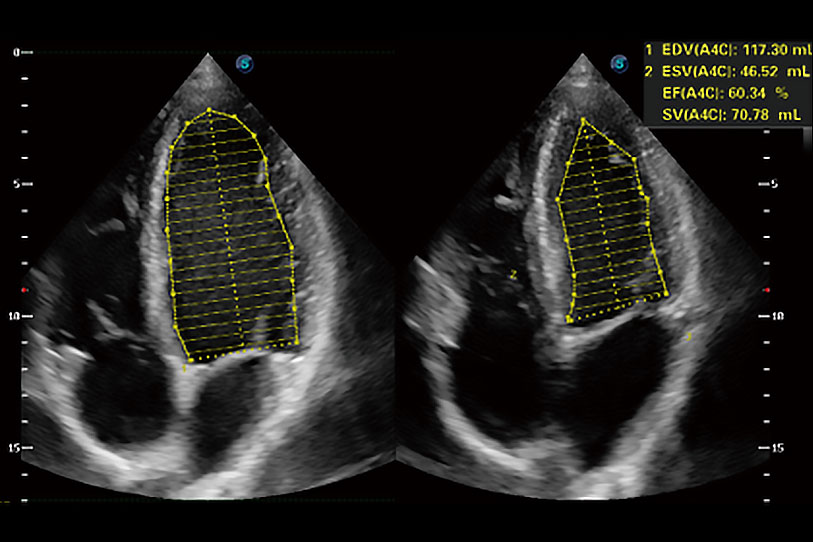

能够基于左心室壁追踪和辛普森法,自动计算射血分数,支持多个可移动点描迹,与手动测量相比,极大节省了动物医生的时间和精力。

具备多种协议可选,同时支持17阶段划分法和专业的SE报告。